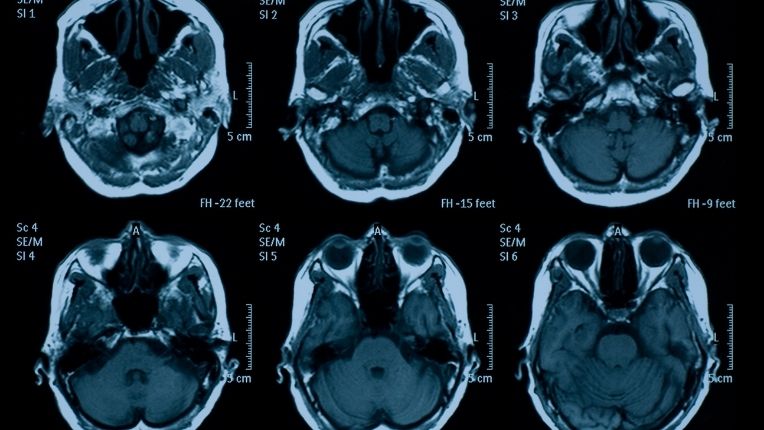

IRM cérébrale

L’IRM cérébrale est un examen d’imagerie médicale. Il permet d’explorer le cerveau et de détecter d’éventuelles anomalies et pathologies cérébrales. Cet examen repose sur l’utilisation d’un champ magnétique et non sur l’émission de rayons X comme le scanner. Découvrez en quoi consiste une IRM du cerveau, dans quel cas elle est prescrite, mais aussi comment elle se déroule.

Une IRM (imagerie par résonance magnétique) cérébrale est un examen d’imagerie médicale qui recourt aux ondes de radiofréquences. Ces ondes traversent le cerveau et sont retranscrites sous la forme d’images très précises sur l’écran de l’ordinateur.

Non invasive et totalement indolore, l’IRM du cerveau permet d’étudier le système nerveux central, mais aussi les différents composants du cerveau. Elle permet de visualiser précisément la substance blanche (partie superficielle) et la substance grise (partie profonde) du cerveau. Mais aussi le système ventriculaire cérébral ainsi que l’état des vaisseaux sanguins (veines, artères). Cet examen est utilisé pour poser un diagnostic sur des symptômes neurologiques et pour détecter des anomalies cérébrales. L’IRM cérébrale peut être réalisée sans ou avec injection d’un produit de contraste (sels de gadolinium) selon les cas.